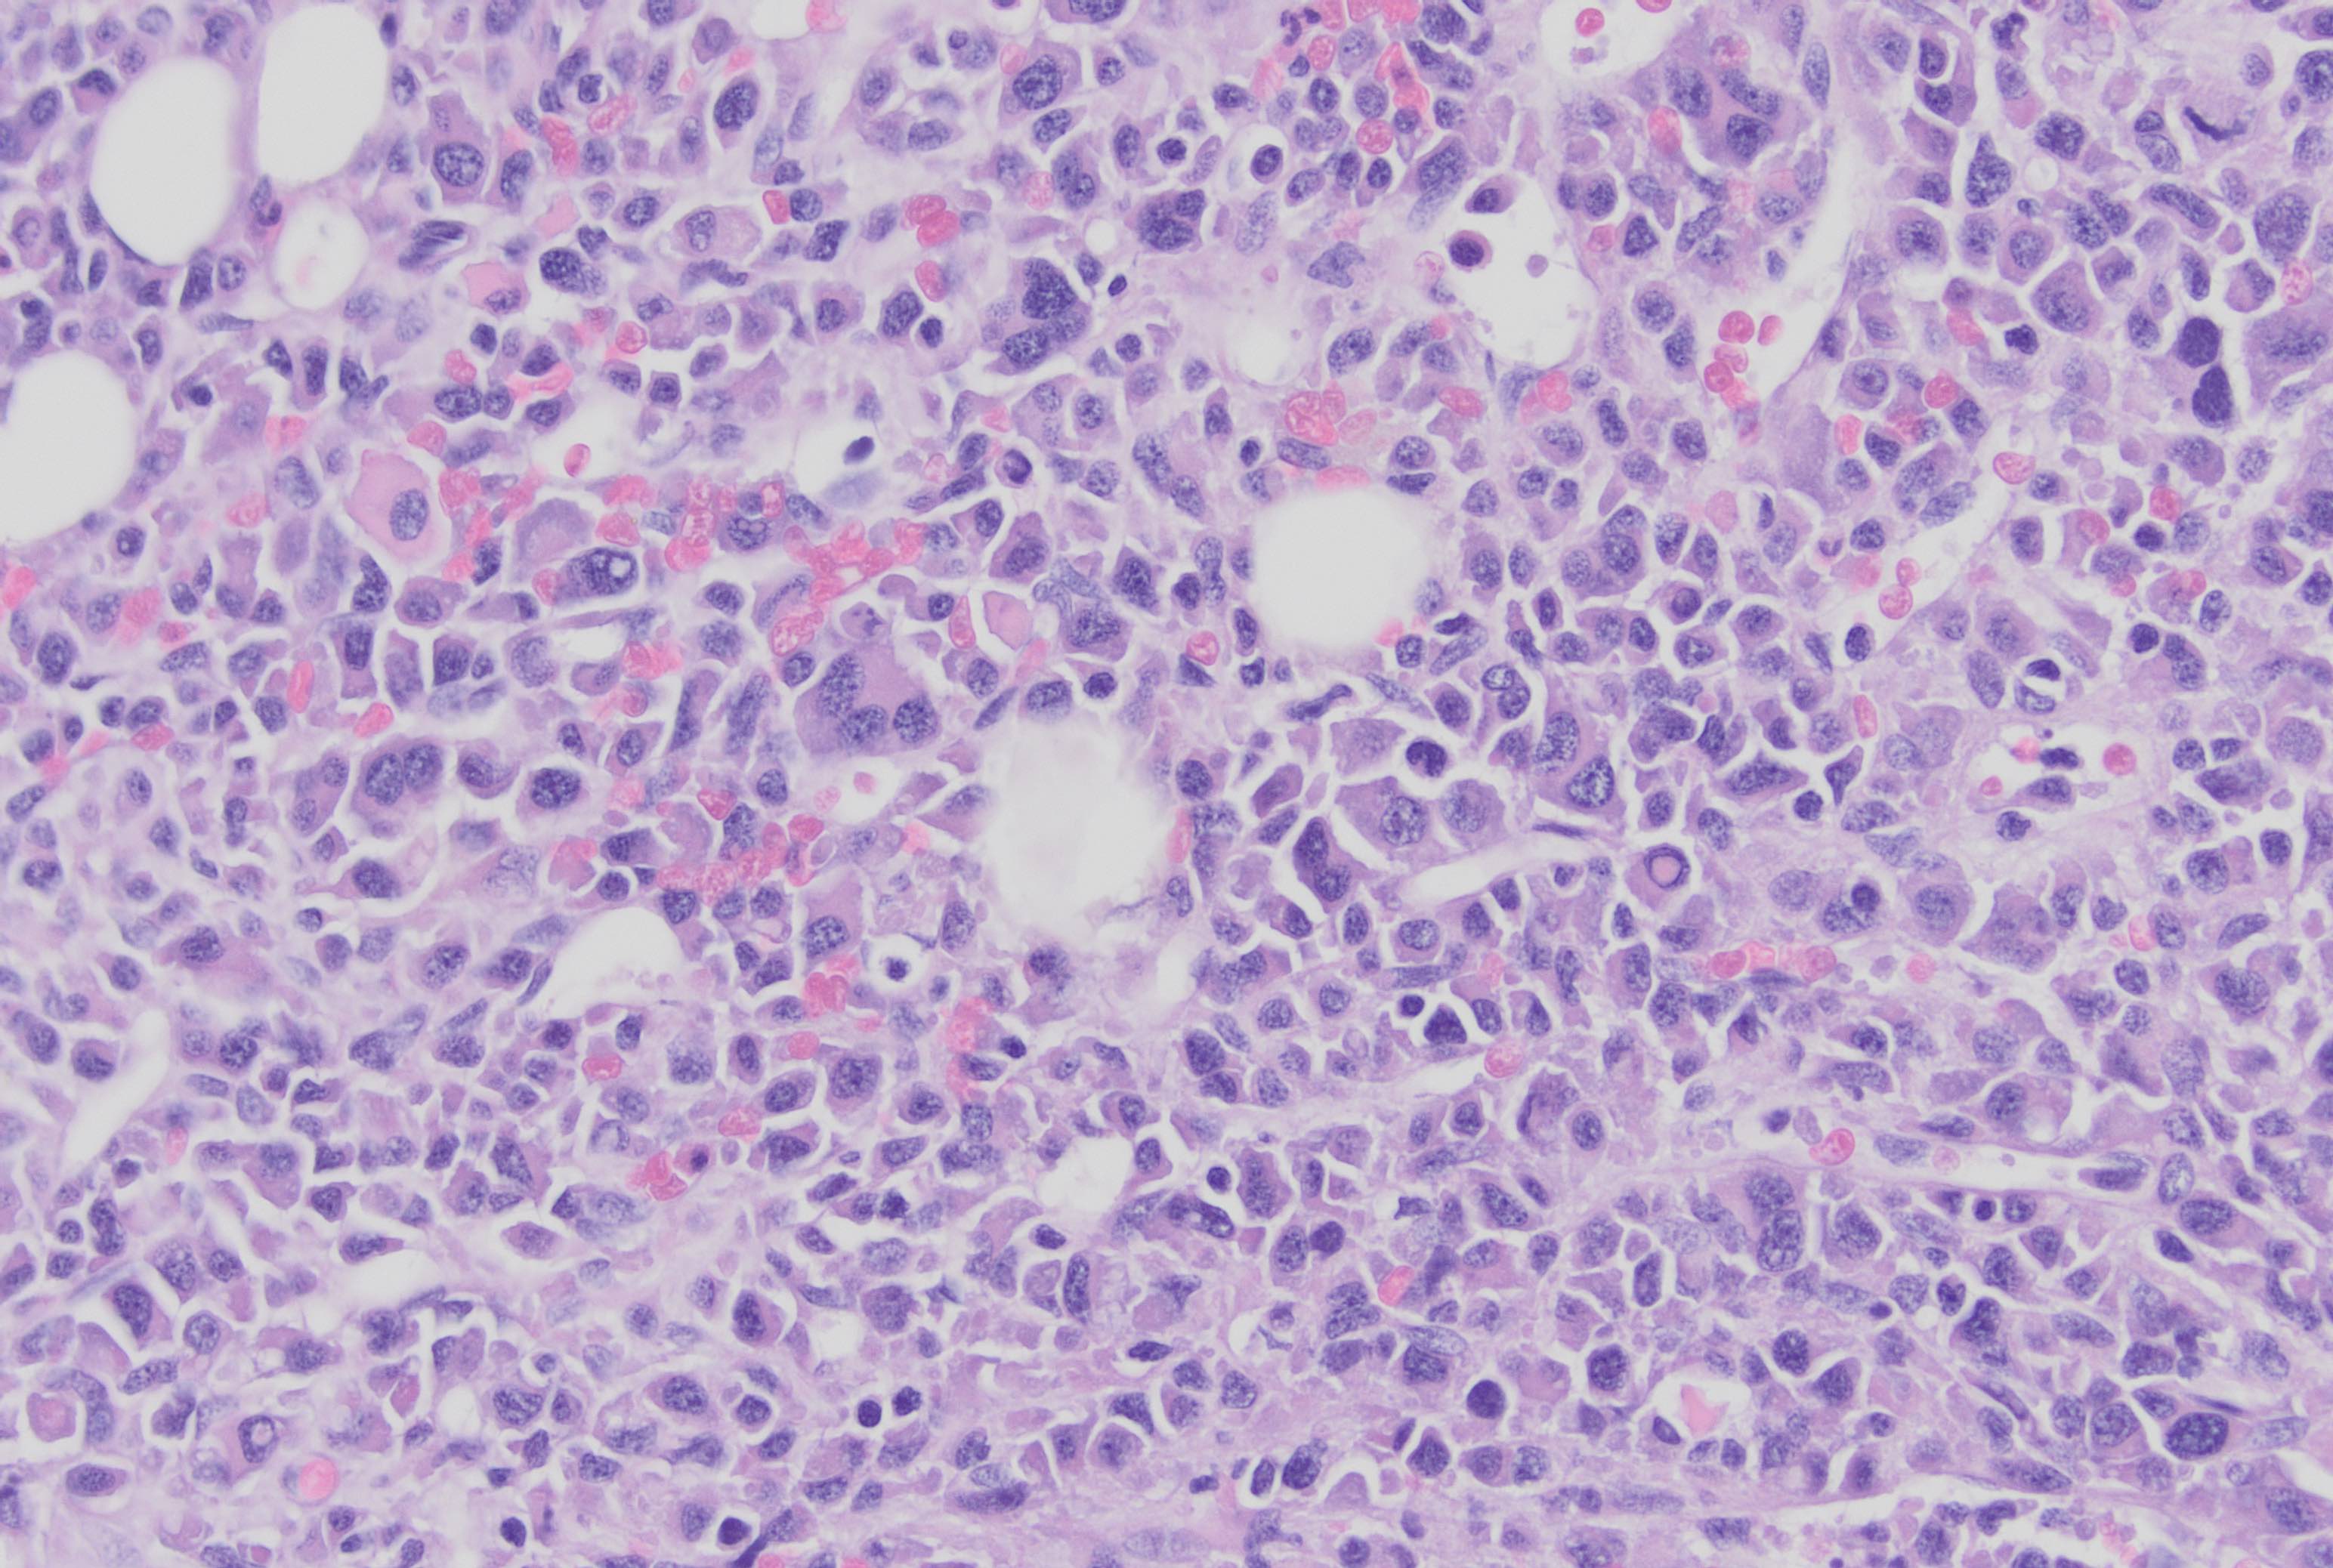

Microscopic (histologic) description

- Core biopsy (Am J Clin Path 1987;87:342):

- Interstitial clusters, nodules or sheets of plasma cells

- Areas of bone marrow may be spared with preserved hematopoiesis, other cases may have diffuse involvement and markedly suppressed hematopoiesis

- Prominent osteoclastic activity may be seen

- IHC to quantify plasma cells (CD138), stains for Ig kappa and lambda to establish clonality

Microscopic (histologic) images

Contributed by Genevieve M. Crane, M.D., Ph.D. and Tapan Bhavsar, M.D., Ph.D.

Cytology description

- Cytology can assess plasma cell morphology (e.g., mature, immature, plasmablastic) but number of plasma cells present may vary substantially from the core biopsy

- Mature plasma cells: oval with abundant basophilic cytoplasm, perinuclear hof, round eccentric nuclei, clock face chromatin and indiscernible nucleoli

- Immature plasma cells: higher nuclear to cytoplasmic ratio, more abundant cytoplasm and hof region compared to plasmablastic, more dispersed chromatin, often prominent nucleoli

- Plasmablastic: less abundant cytoplasm with little or no hof region, fine reticular chromatin, large nucleus (> 10 microns) or large nucleolus (> 2 microns) (Blood 1998;91:2501)

- Pleomorphic: multinucleated, polylobated